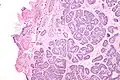

| Micrograph of a Sertoli cell nodule. H&E stain. | |

Sertoli cell nodules are unencapsulated nodules that consist of:[2][3][4]

- cells arranged in well-formed tubules (that vaguely resemble immature Sertoli cells), with

- bland hyperchromatic oval/round nuclei that are stratified, and

- may contain eosinophilic (hyaline) blob in lumen (centre).

Micrograph of a Sertoli cell nodule. H&E stain.